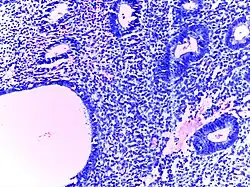

Lymph node metastasis | Lymph node showing metastases from colorectal carcinoma | Category: Lymph node metastases | Lymph node metastasis |